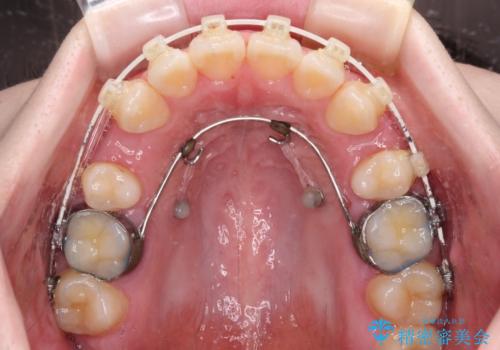

上顎前歯をしっかりと後方に移動させるため、口蓋側にアンカースクリューと補助装置を併用し、上下左右の第一小臼歯4本を抜歯し、ワイヤー装置にて矯正治療を行うこととしました。

また、舌のトレーニングをしっかりと行うことで、突出癖改善を試みることとしました。